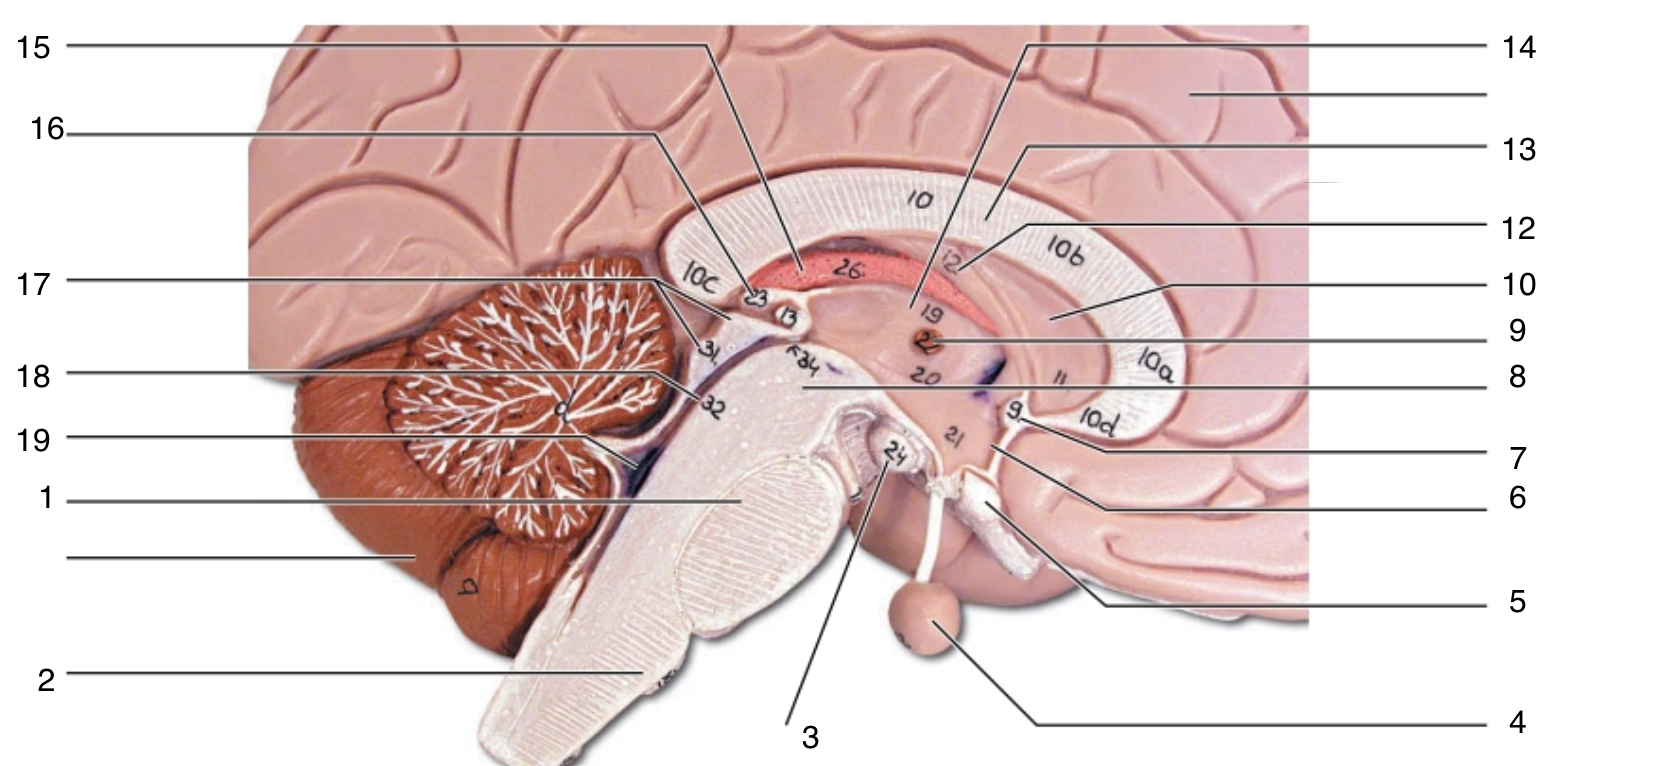

Brain Stem

20 Terms

1

pons

2

medulla oblongata

3

mammillary body

4

pituitary gland

5

optic chiasma

6

hypothalamus

7

anterior commissure

8

midbrain

9

interthalamic adhesion

10

septum pellucidum